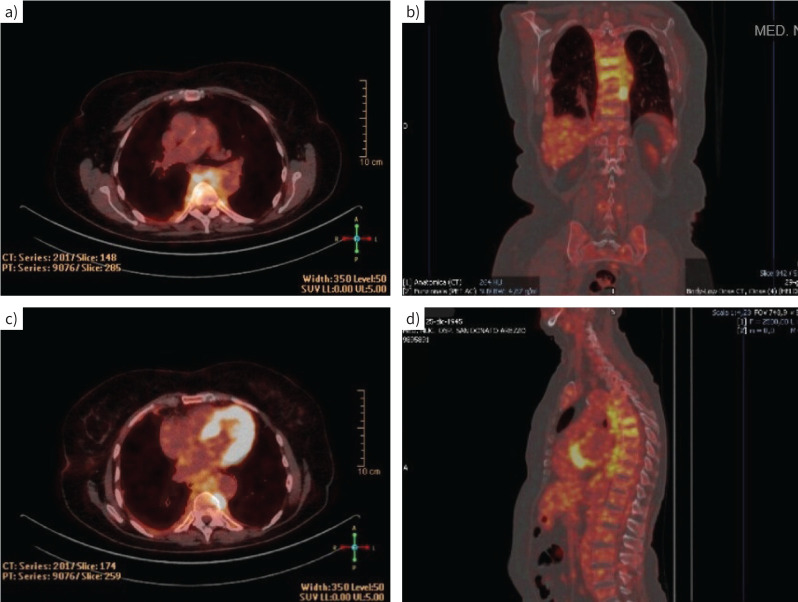

Abstract Image